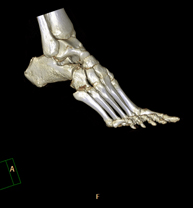

- TC Tobillo-pie

Exploración radiológica que mediante un sistema de rayos X y detectores que giran alrededor del paciente, reconstruyendo las imágenes por ordenador (TC Multidetector), permite el estudio de huesos, músculos y articulaciones del tobillo y el pie.